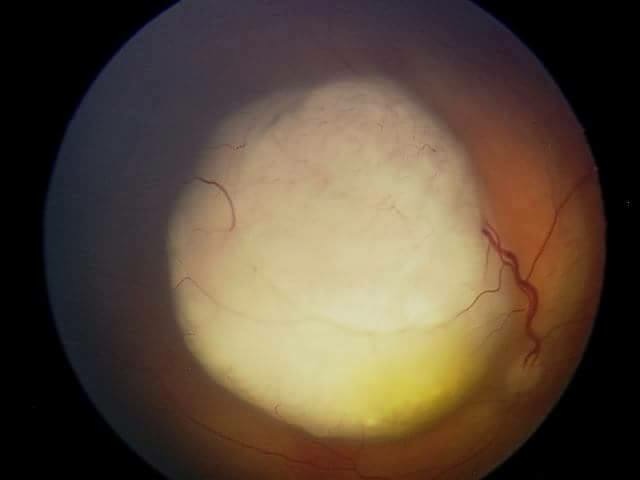

Dr. Abramson and his team recommend ophthalmic artery chemosurgery to treat the retinoblastoma. This type of chemosurgery allows chemoterapy to be injected directly into a blood vessel in the eye. This treatment method, if performed before the tumor spreads, has a 99 percent cure rate. This why it is extremely imporant to undergo this treatment, as soon as possible. Below the attached eye photo shows the size of the cancer tumor in baby Tymon's eye as of March.

This is an image of Tymon's eye, showing a large malignant tumour - retinoblastoma.

This is an image of Tymon's eye, showing a large malignant tumour - retinoblastoma.

Dr. Abramson and his team recommend ophthalmic artery chemosurgery to treat the retinoblastoma. This type of chemosurgery allows chemoterapy to be injected directly into a blood vessel in the eye. This treatment method, if performed before the tumor spreads, has a 99 percent cure rate. This why it is extremely imporant to undergo this treatment, as soon as possible. Below the attached eye photo shows the size of the cancer tumor in baby Tymon's eye as of March.

This is an image of Tymon's eye, showing a large malignant tumour - retinoblastoma.

This is an image of Tymon's eye, showing a large malignant tumour - retinoblastoma.  The tumour within Tymon's eye can be seen as the white glare in his right pupil.